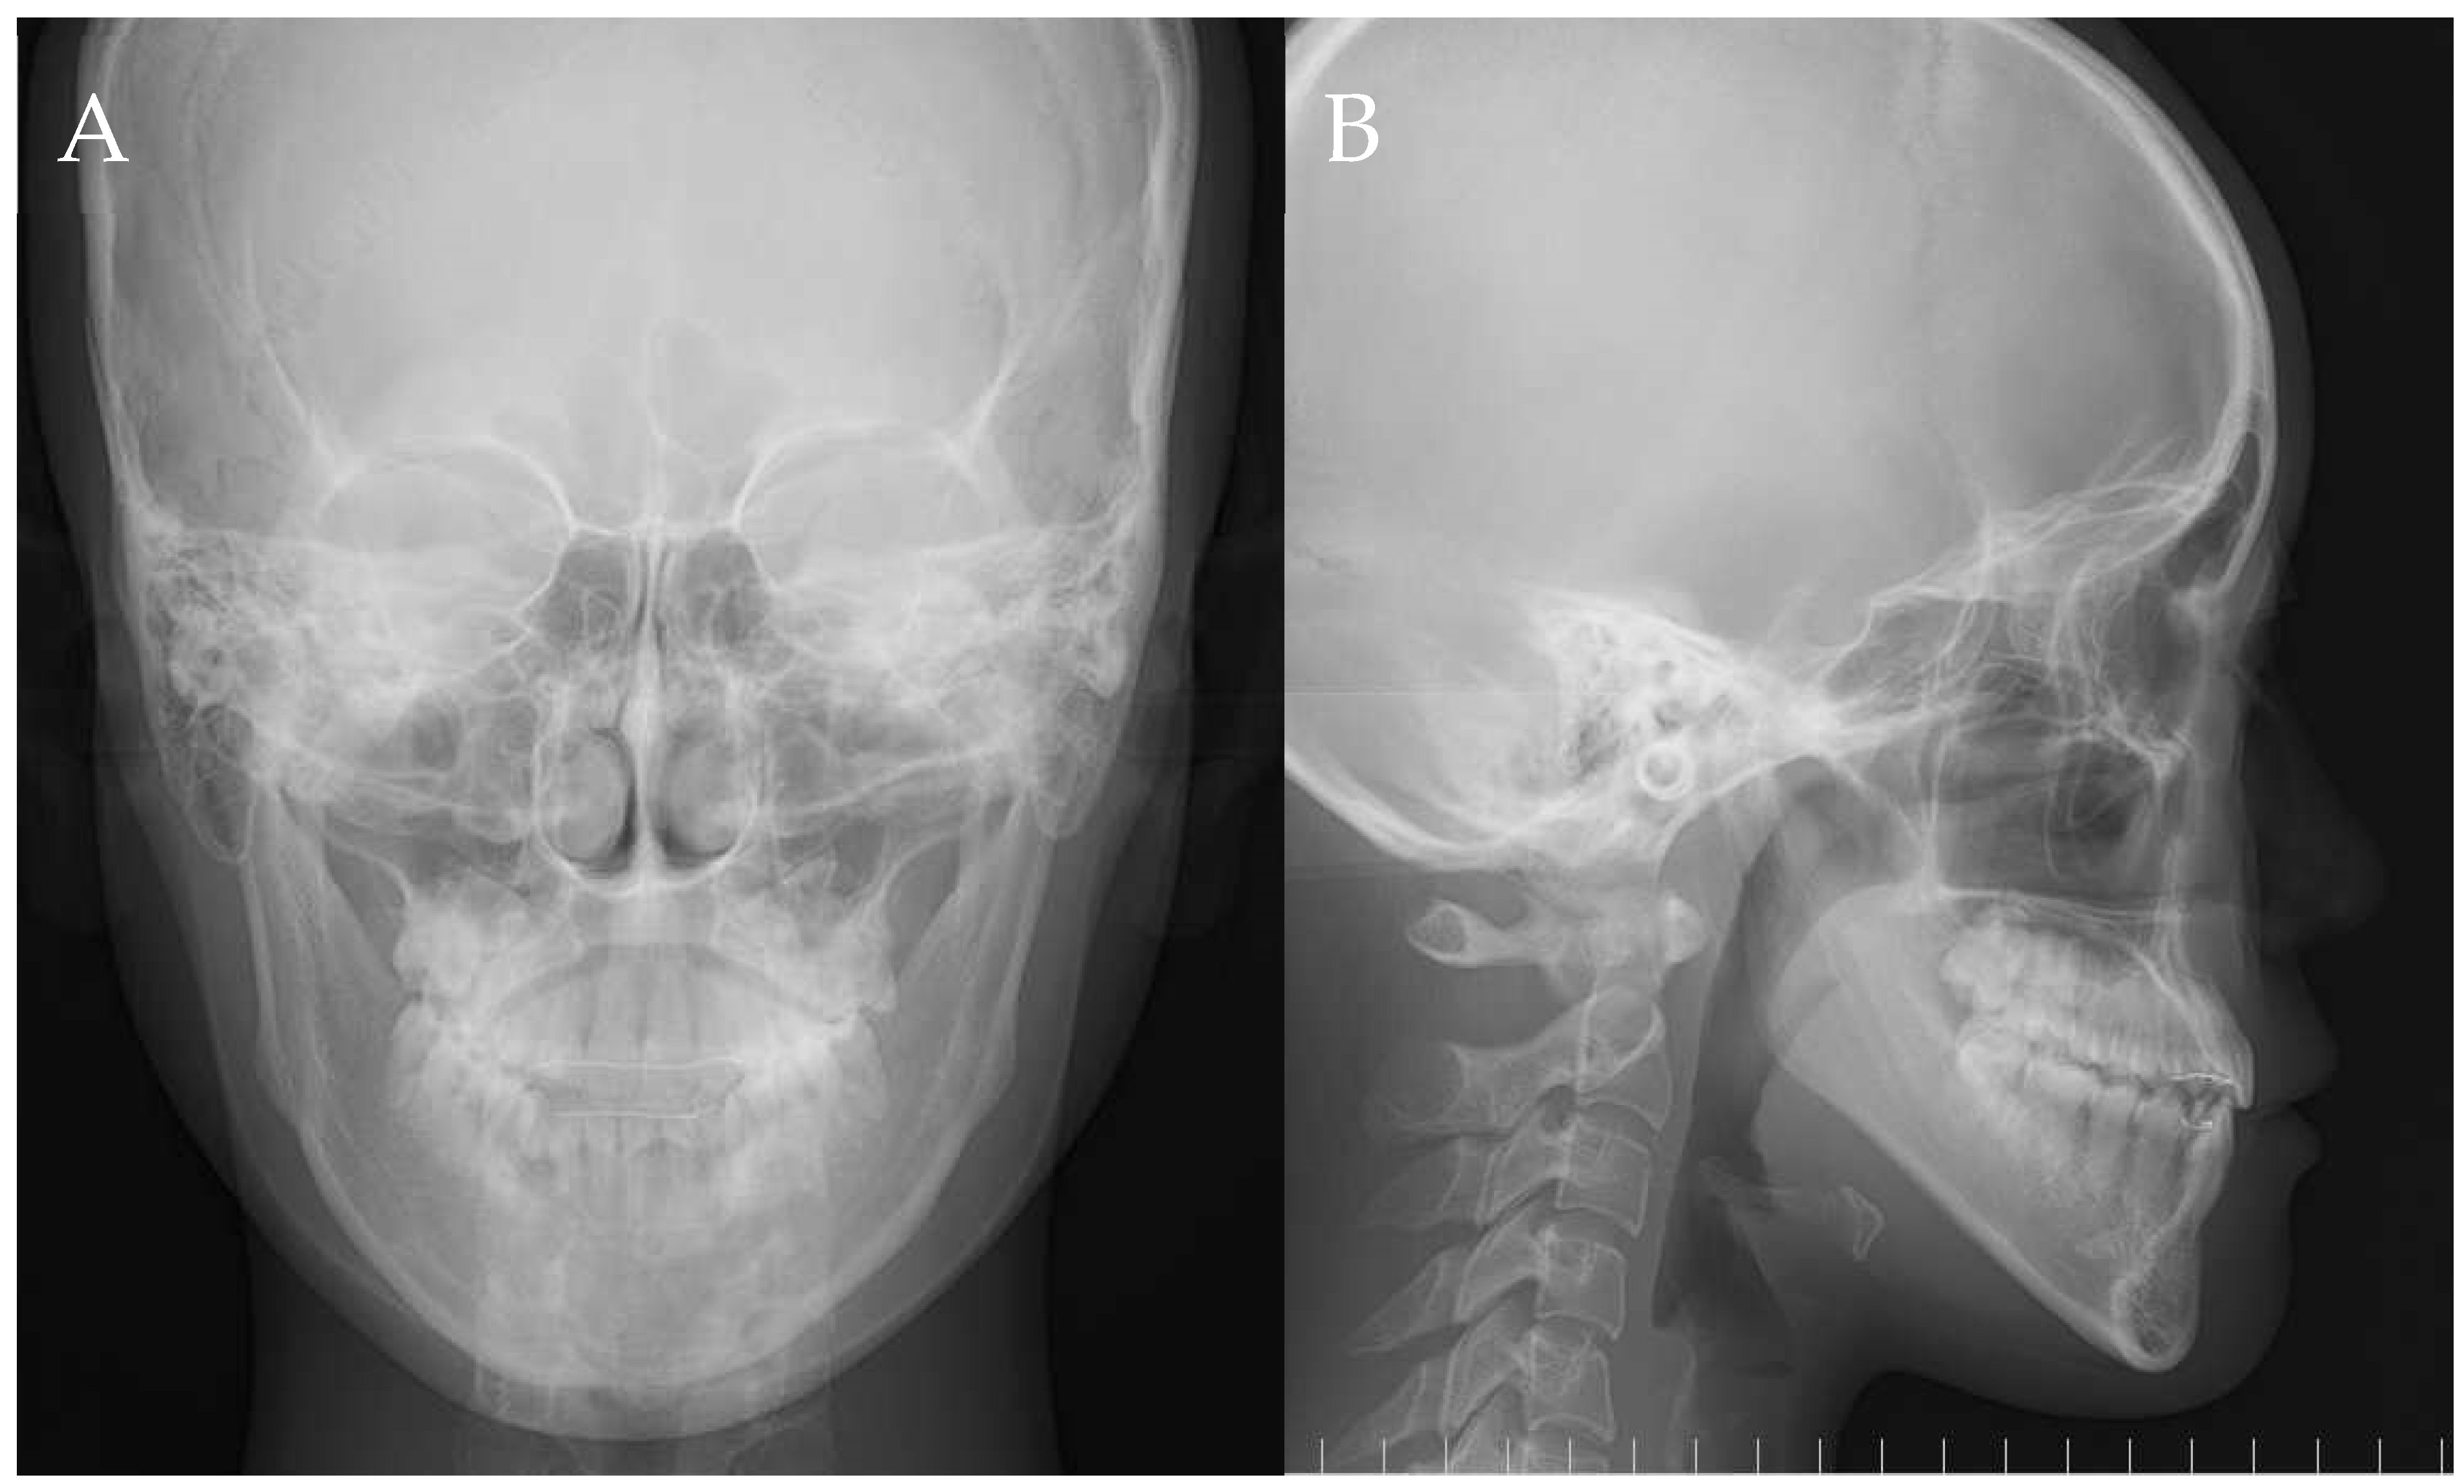

3. Results

| Measurements | Pre-Treatment | Post-Treatment |

|---|---|---|

| SNA (°) | 81.5 | 81.5 |

| SNB (°) | 81.3 | 82.8 |

| ANB (°) | 0.2 | −1.3 |

| FMA (°) | 36.2 | 36.5 |

| FMIA (°) | 64.3 | 74.6 |

| IMPA (°) | 79.5 | 68.9 |

| U1-SN (°) | 110.9 | 106.9 |

| U1 to A-Pog (mm) | 7.7 | 6.2 |

| L1 to B-Pog (mm) | 7.1 | 4.0 |

| E-line: Upper (mm) | 0.1 | −0.9 |

| E-line: Lower (mm) | 2.4 | 0.1 |